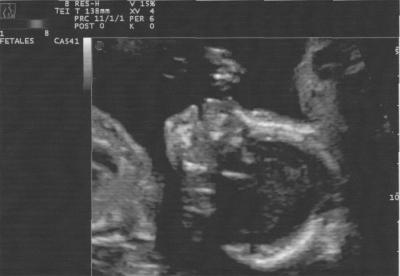

Leider gabs nicht viele richtig schöne, da Madame sich meist mit dem Hinterkopf präsentiert hat... Aber hier eins, das ganz gut wurde

Bild zu Bild von der VU gestern - Forum für Juni - Mamis